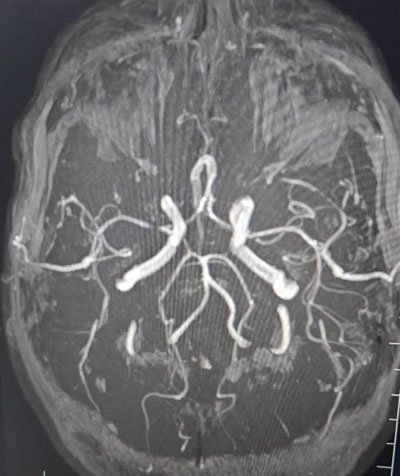

MRA showed a focal short-segment (2.3 mm) tight stenosis of the right M1 segment of the middle cerebral artery.